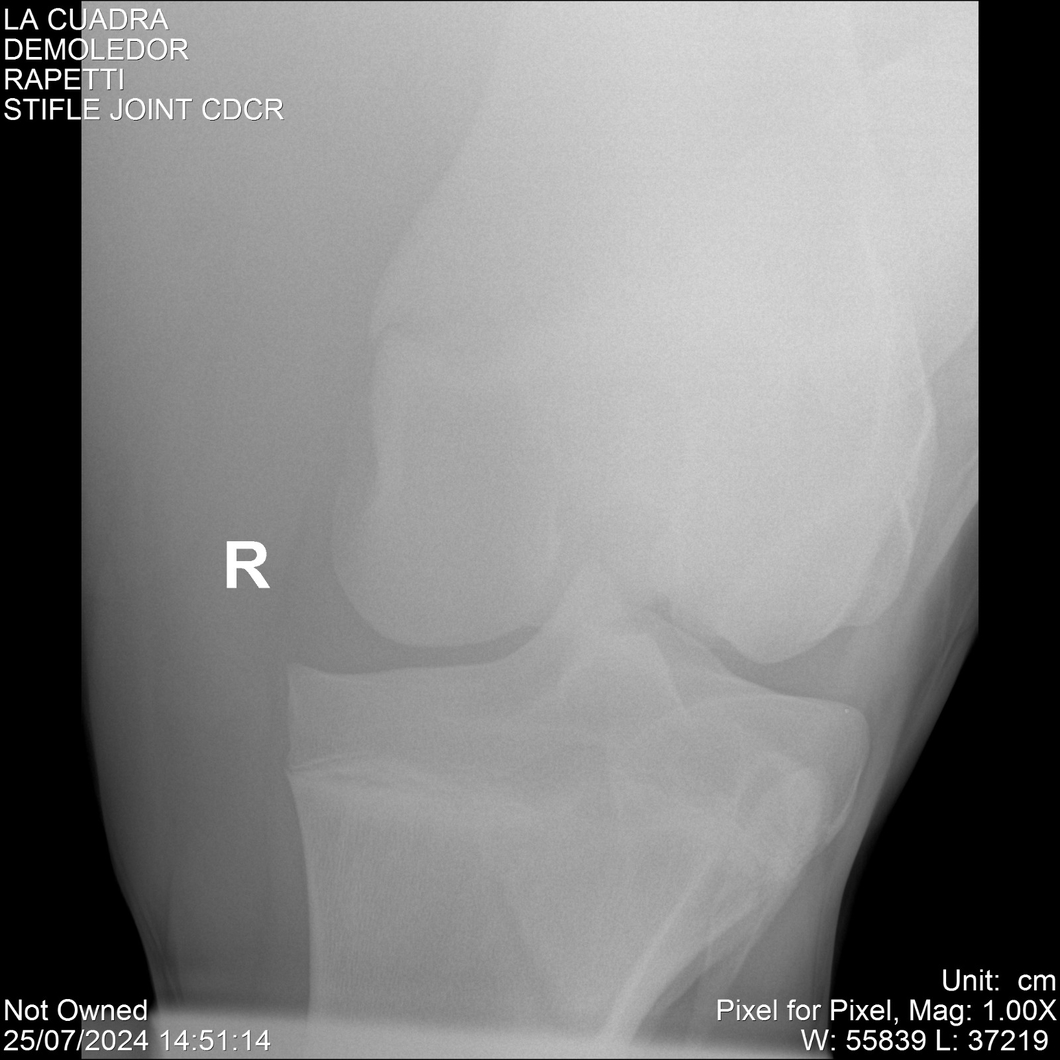

LOTE 14, DEMOLEDOR 🔥 🔥 🔥 Lote Anterior Volver al remate Lote Siguiente Ficha Contacto Montevideo - Ficha del Lote Identificador: #284454 Categoría: Yeguarizos Montevideo - 89 Visualizaciones ClicData Contacto Empresa: Abelenda N. R., Walter Hugo Nombre*: Teléfono* : E-mail* : Mensaje Enviar Registrese gratis Este contenido Exclusivo está disponible sólo para usuarios registrados Ingresar